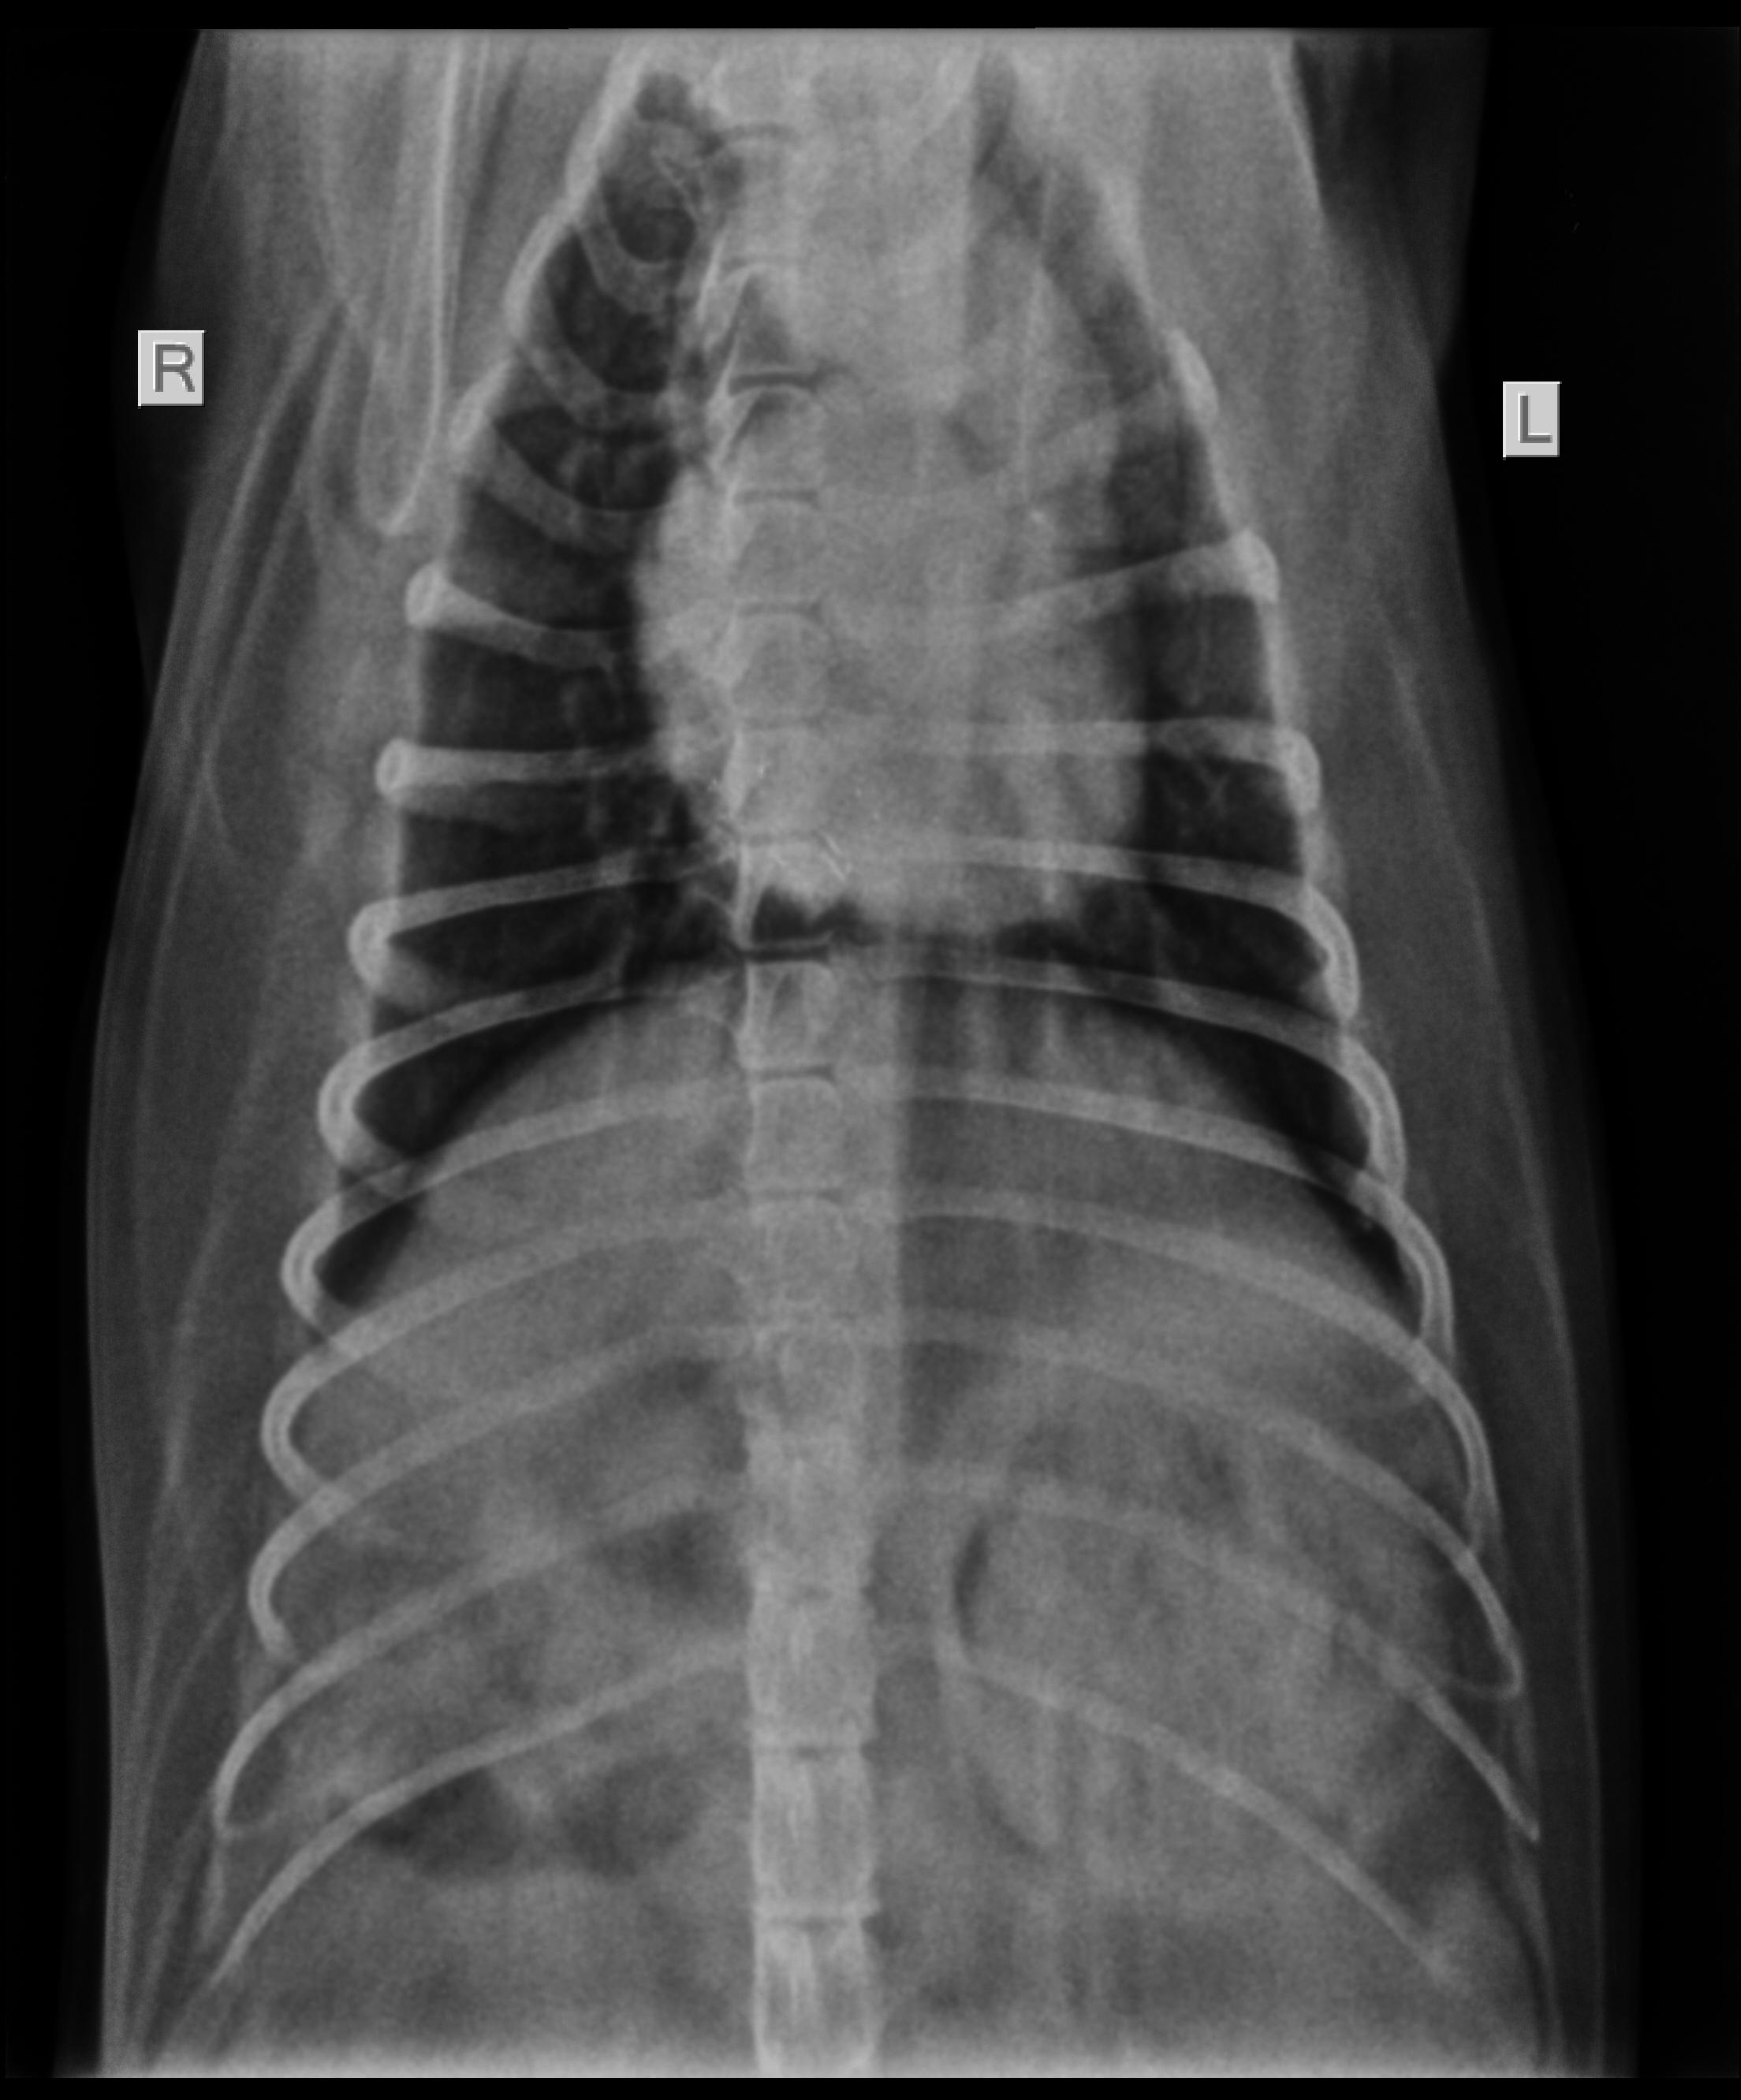

I have a six year old golden retriever. She has lately been diagnosed with lung tumour- a mass on her lower right chest cavity. Her earlier symptoms included difficulty in breathing, snoring at night and lately she found it difficult to bend and eat as her tumour was choking her. She does not have any weight loss nor is she lethargic. Can you please suggest what this tumour impplies as I am very worried.

Thanks for using Petco Pet Education Center, formerly Petcoach! Lung tumors are uncommon in the dog. The most common tumors are adenocarcinoma and histiocytic sarcoma though other tumor types are possible. This can be determined in most cases by performing a FNA (fine needle aspirate) of the mass. The treatment for it will depend on the exact type and also the extent of disease. If this is solitary and has not spread then surgery would be the treatment of choice which may be followed by chemotherapy. The prognosis will depend on many factors like the type of tumor, size, spread of the tumor and treatment selection though cures are rare for any of these tumors. Good luck and best wishes for Cassie!